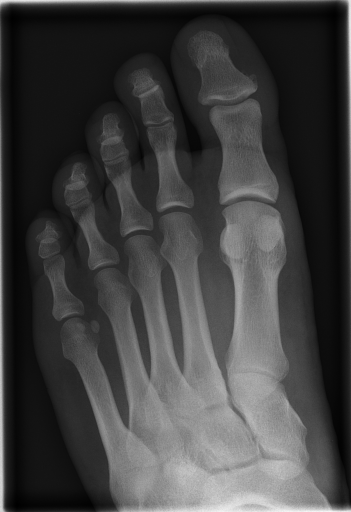

The Image Retrieval in Medical Applications (IRMA222http://irma-project.org/) database is a collection of 14,410 x-ray images that have been randomly collected from daily routine work at the Department of Diagnostic Radiology of the RWTH Aachen University333http://www.rad.rwth-aachen.de/. The downscaled images were collected from different ages, genders, view positions, and pathologies [3].

Figure 3 shows some samples images from IRMA dates along with their corresponding IRMA codes.